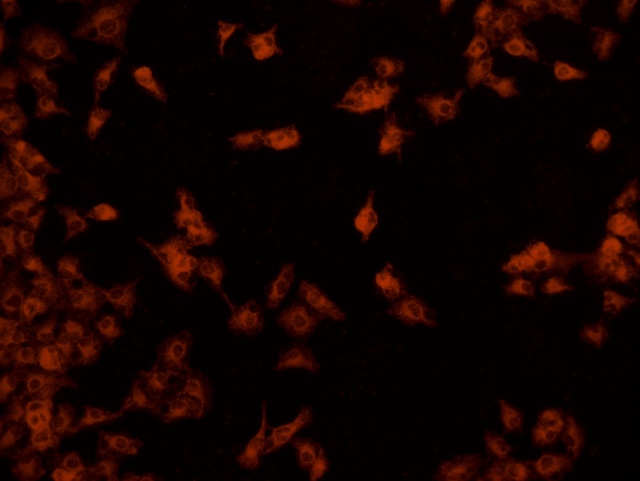

南華大學(xué)在生物醫(yī)學(xué)研究領(lǐng)域一直走在學(xué)術(shù)前沿,近日,該校引進(jìn)Mshot明美的倒置熒光顯微鏡MF52-N,搭配顯微鏡相機(jī)MSX2,為細(xì)胞切片標(biāo)本的研究提供了強(qiáng)大的技術(shù)支持,進(jìn)一步提升了科研實力。

MF52-N倒置熒光顯微鏡以其數(shù)顯LED熒光模塊和深度優(yōu)化的光路設(shè)計,成為細(xì)胞切片觀察的理想選擇。其簡單易用的熒光激發(fā)操作,大大降低了實驗難度,提升了工作效率。同時,該顯微鏡還能提供高質(zhì)量的相襯、熒光和明場成像,確保科研人員能夠捕捉到細(xì)胞切片的每一個細(xì)節(jié)。

在南華大學(xué)的實驗室中,科研人員正借助這套先進(jìn)的顯微系統(tǒng),對細(xì)胞切片標(biāo)本進(jìn)行深入探索。

此外,MSX2顯微鏡相機(jī)的加入,更是如虎添翼。這款相機(jī)以其高分辨率和敏銳的圖像捕捉能力,記錄了實驗過程中的每一個重要瞬間,為數(shù)據(jù)分析與論文發(fā)表提供了有力支持。